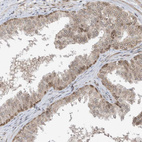

Immunohistochemical staining of human endometrium shows moderate positivity in nuclear membrane in glandular cells.